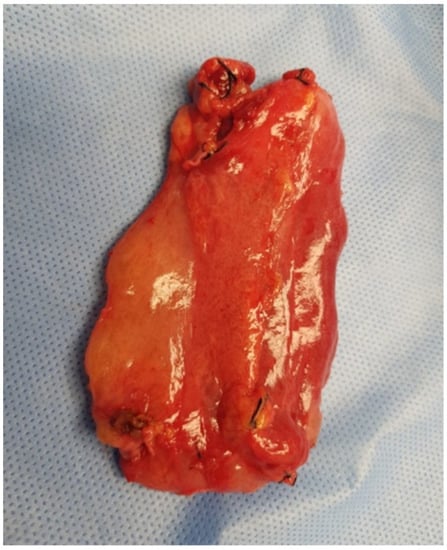

The patient was qualified for elective surgery. The presence of an approximately seven-cm long soft tissue extending along the lesser curvature of the stomach, closely connected to the stomach wall, was found intraoperatively (Figure 2). The tumour penetrated the gastrohepatic ligament, but did not reach the liver. The lesion did not penetrate the retroperitoneal space or infiltrate the pancreas. The tumour was completely removed without gastric wall resection (Figure 3). After removal of the lesion, the serosa of the lesser curvature of the stomach was secured with a continuous PDS 4/0 suture (Figure 4).

Figure 2. Intraoperative image—The tumour was close to the lesser curvature of the stomach. The arrows indicate: the lesser curvature of the stomach (red arrow), and the anterior surface of the tumour (black arrow).